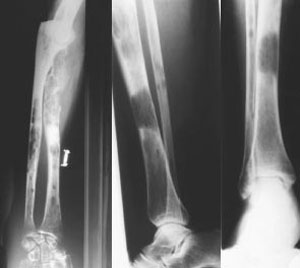

- кости разрушаются и происходят частые переломы, позвонки могут оседать, вызывая сдавливание спинного мозга, остеопороз и т.п.;

В пределах миеломы ткань кости будет постоянно рассасываться, в губчатой кости будут пропадать перекладины и истончаться кортикальный слой. Он может полностью разрушиться, в этом случае опухоль прорастет под надкостницу, поднимет ее и будет продолжать расти на кости.

Делают рентген, проводят анализы крови и мочи, также можно делать МРТ при множественной форме.